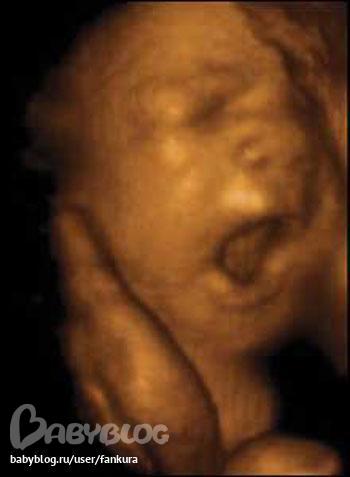

Анют а это вы в 3Д УЗИ? Мне интересно так все хорошо видно))) Мы на следующей недели пойдем))))

да сходите)все советуют)это же новое что то)))))классс